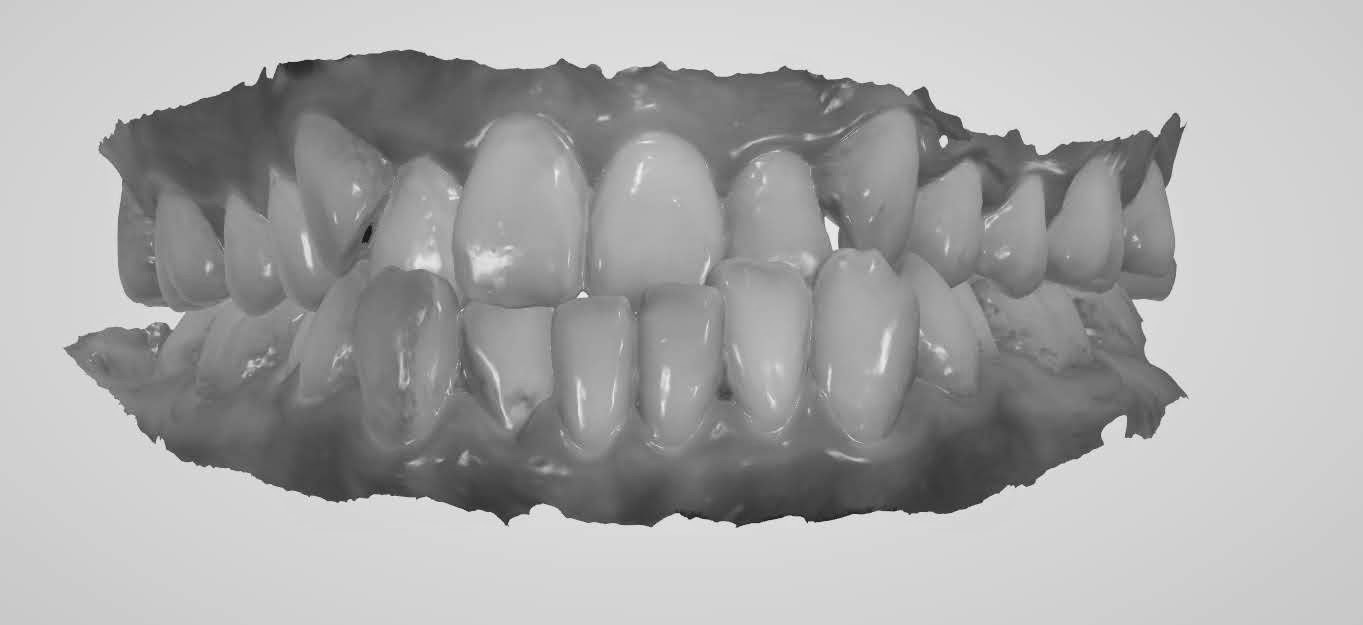

能讓你清楚的看到每顆牙齒的長相、咬合狀況等,甚至連蛀牙、牙結石都照的很清楚,這樣當醫師在說明你的口腔狀況時,才能夠更了解且更快進入狀況

咬合狀況,因為有點亂直接拉黑,以免嚇到大家...